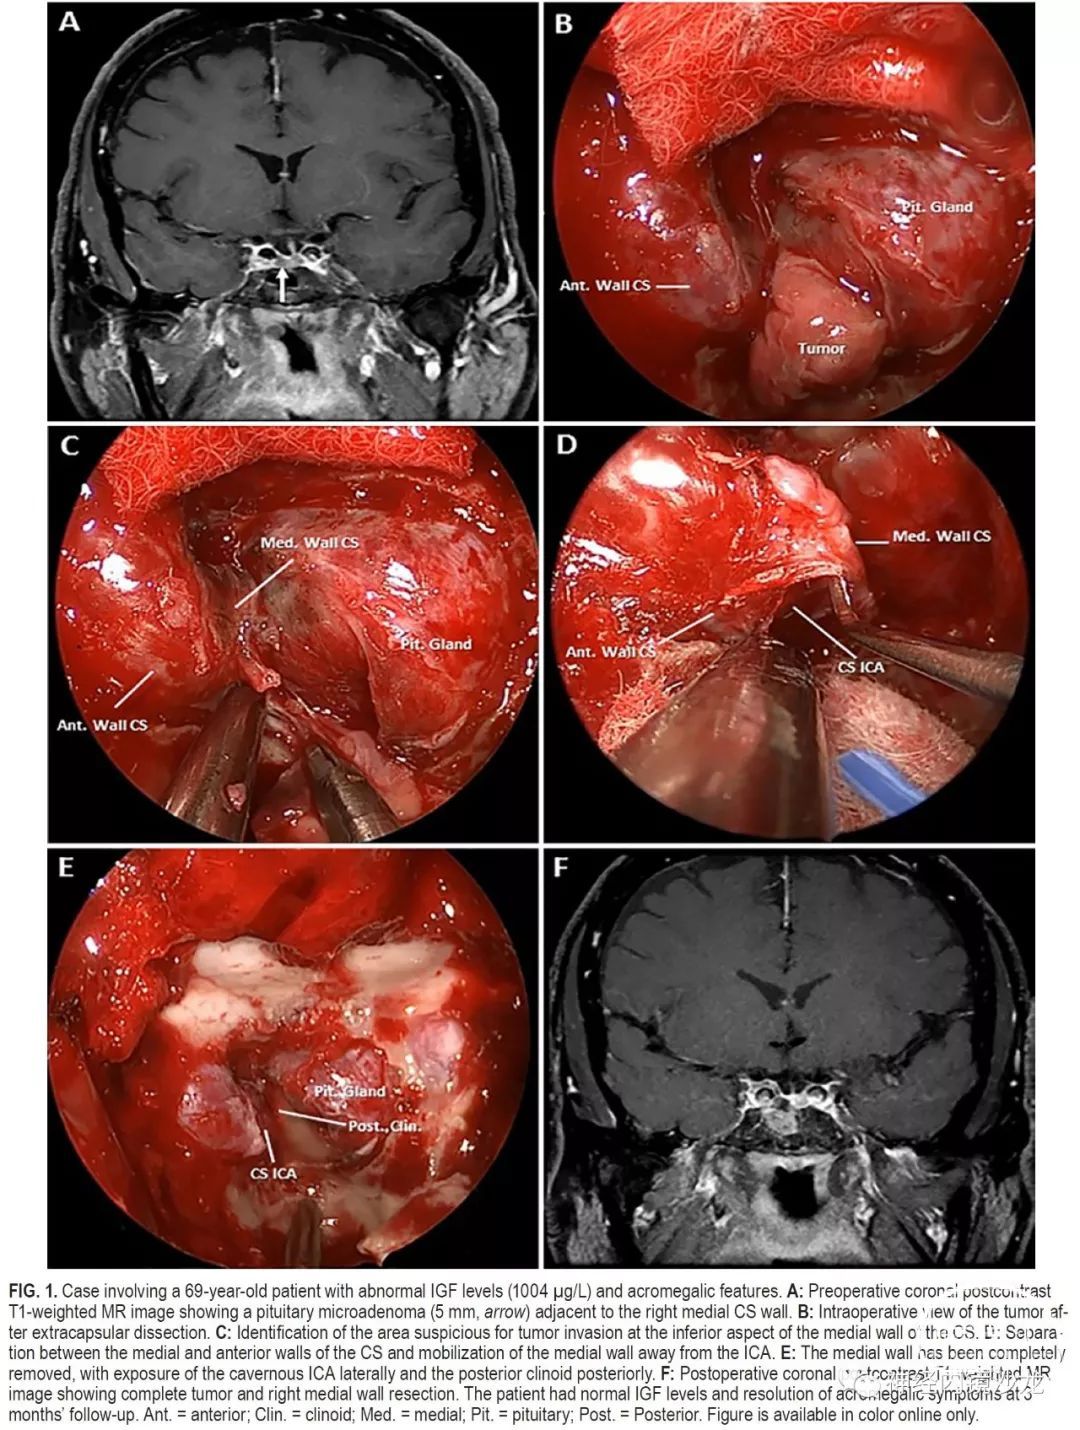

目的:垂体腺瘤常侵袭海绵窦(CS)的内侧壁,但由于存在血管和颅神经损伤的风险,通常不能外科手术切除。本研究的目的是报告一组大宗采用基于解剖学基础、分步选择性地手术切除海绵窦内侧壁的侵袭性垂体腺瘤病例的手术结果。

方法:对作者所在机构数据库进行了研究分析,筛选术中发现单纯侵犯内侧壁且采用内镜经鼻入路选择性切除海绵窦内侧壁的垂体腺瘤病例。排除侵袭海绵窦超出内侧壁的病例。对患者的并发症、切除率和缓解率进行评估。

结果:50例患者符合本研究的条件,15例(30%)非功能性腺瘤和35例(70%)功能性腺瘤;包括16例生长激素、10例催乳素和9例促肾上腺皮质激素(ACTH)腺瘤。非功能性腺瘤的平均肿瘤大小为2.3cm,功能性腺瘤的平均肿瘤大小为1.3cm。放射学检查,11例(22%)为Knosp 1级,23例(46%)Knosp 2级,16例(32%)Knosp 3级。根据术中判断和术后MRI,所有病例均实现肿瘤全切。对于功能性腺瘤患者,平均随访时间为30个月(范围4-64个月),对于非功能性腺瘤患者,平均随访时间为16个月(范围4-30个月)。根据最后一次随访结果,34例(97%)功能性腺瘤未采用辅助治疗即获得完全生化缓解(使用现行标准)。非功能性腺瘤的患者,未见影像学复发。50名患者中共切除了57侧内侧壁。组织学证实,93%的非功能性腺瘤和83%的功能性腺瘤中存在内侧壁侵袭。没有死亡或颈内动脉损伤病例,平均失血量为378ml。4名患者(8%)出现新发短暂性颅神经麻痹,其中2名患者需要再次手术清除血凝块和脂肪填塞物。未出现永久性颅神经麻痹。

结论:海绵窦内侧壁可以安全有效地切除,并发症低,完全切除和症状缓解率极佳。这种基于解剖学的手术技术的长期疗效,需要更多随访数据进一步确定。该技术只能由非常有经验的鼻内镜颅底团队进行。